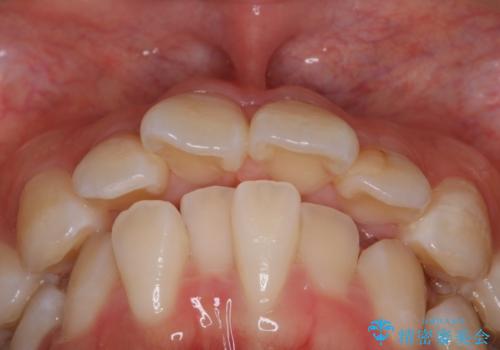

- 前歯のがたつきと口元を気にされて来院されました。

上下4番目の歯を抜歯してがたつきを改善しながら口元を下げる治療計画を立てました。